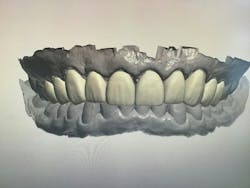

Once the patient accepts treatment and is on board for the crown lengthening as proposed, a surgical guide stent must be created and printed for approximation of the new crown margins. Using the smile creator Exocad, a digital mock-up of the final margins of the newly lengthened teeth is generated. The patient can be presented with the simulated smile and accept the look of the mock-up before digitally fabricating the surgical guide needed to achieve said results.

Utilizing a facially driven treatment plan, the facial photographs were merged with the CBCT scan to assess bone levels, and the central incisors were digitally planned to exhibit a new length of 11.5 mm, to enhance the patient’s long facial structure. The new width of the veneers could then be generated to be 85% of this measurement to achieve the golden proportion for optimal esthetics. Once the surgical guide is designed in Exocad to achieve these coronal margins, the guide design is exported to SprintRay to be printed with a snug fit for accurate coronal margination for the final restorations later on.

New scans of the patient’s mouth were taken eight weeks after the osseous surgery, prior to the minimal veneer preparations. The original digital plan then can be evaluated, which typically involves minor changes. The next phase design would be printed in the office following sharing the STL files (stereolithography). This allows the office to create a restorative matrix and reduction guide for the dentist. Careful preparation was utilized so as to stay within enamel only, which many studies have shown allows for more predictable bonding and longevity of veneer restorations. Standard tissue retraction methods were used, and the preps were scanned with iTero 5D Plus. The provisionals created from the digital plan would allow the patient to test-drive the new smile prior to the final 10 porcelain restorations being placed. The patient was seen a few days after his preps to allow any modifications before the final 10 e.max pressable veneers were created.